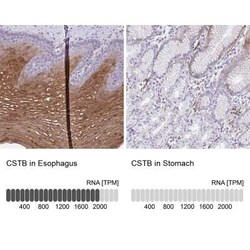

Cystatin B/Stefin B Antibody, Novus Biologicals™

Cystatin B/Stefin B Polyclonal antibody specifically detects Cystatin B/Stefin B in Human samples. It is validated for Immunohistochemistry, Immunohistochemistry (Paraffin)

| Immunohistochemistry 1:50 - 1:200, Immunohistochemistry-Paraffin 1:50 - 1:200 | |